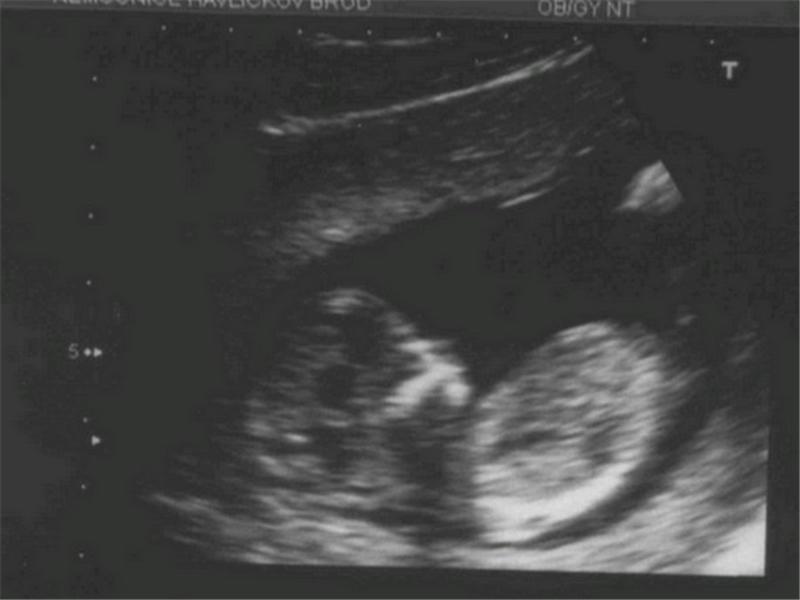

fotečka pomalu v životní velikosti ve 13.týdnu